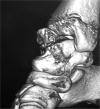

Three-dimensional CT scan reconstruction; anteroposterior view of the ankle.

Figure 4